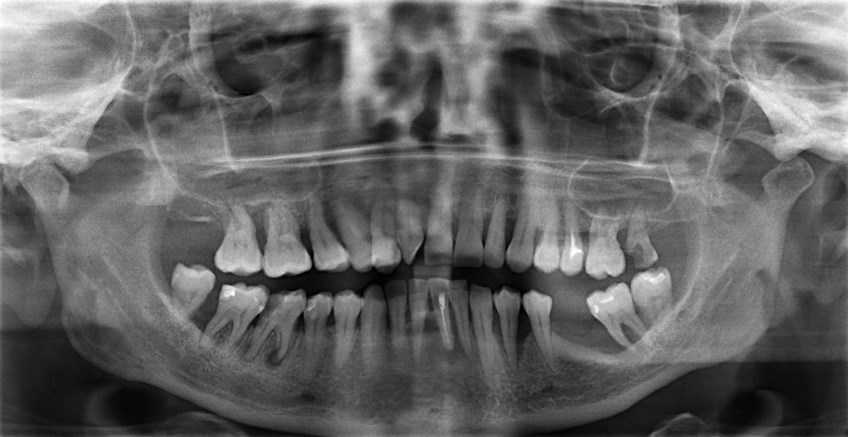

- Осмотр полости рта, проведение рентгенографического исследования и выявление возможных противопоказаний. В их число входят онкологические заболевание, сахарный диабет, аллергия на ультрафиолет, стоматологические болезни в активной стадии. Также отбеливание противопоказано беременным и людям младше 18 лет.

Также для дифференциальной диагностики, то есть точного определения заболевания среди ряда похожих, может понадобиться рентгенологическое исследование. Его часто проводят сразу на первой консультации, хотя могут и назначить отдельно, иногда даже отправив в другую клинику – далеко не везде есть рентгенологические установки.